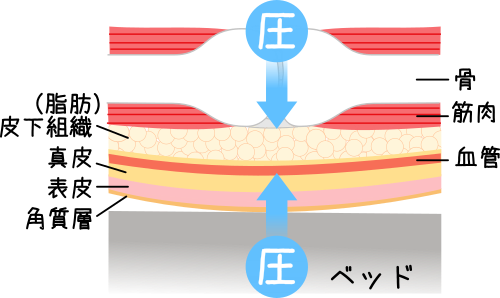

褥瘡とは?定義・原因・看護ケアについて解説レバウェル看護 お役立ち情報。

急性期の褥瘡と慢性期の褥瘡とは浅い褥瘡、深い褥瘡進展過程。

急性期の褥瘡と慢性期の褥瘡とは浅い褥瘡、深い褥瘡進展過程。

褥瘡 床ずれ とは? 原因と症状、予防法についてHeartPlus ハートプラス。

褥瘡とは?定義・原因・看護ケアについて解説レバウェル看護 お役立ち情報。